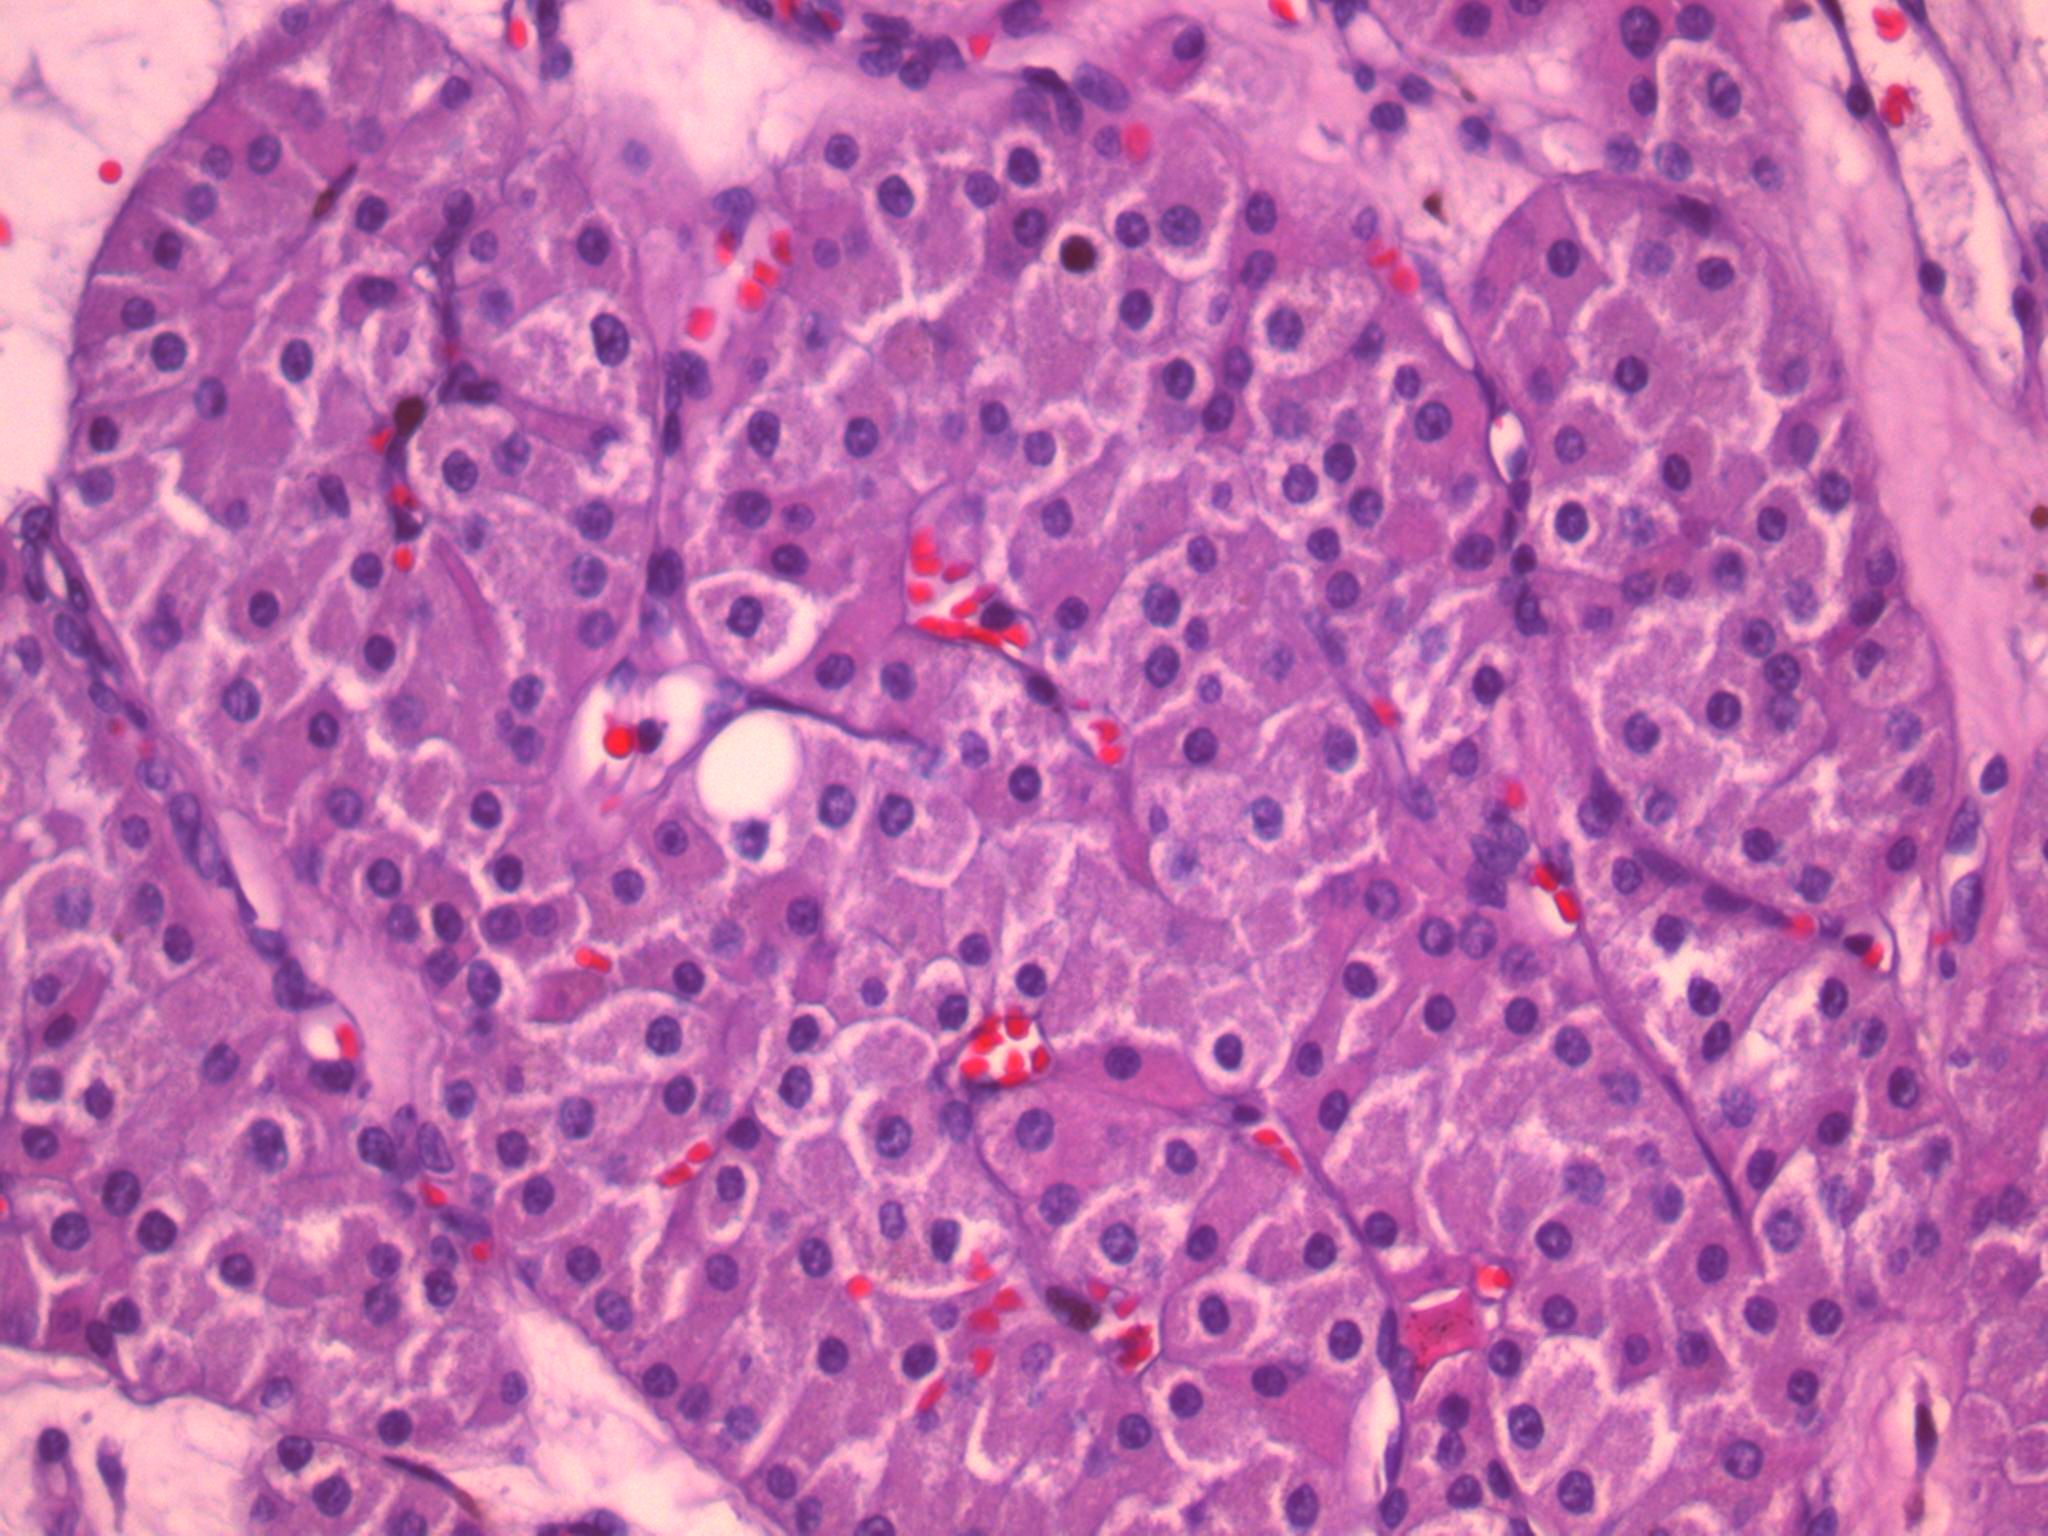

Case ID: 464

Consensus grade: I would not grade this tumor

Case description (by case creator):

Oncocytic neoplasm